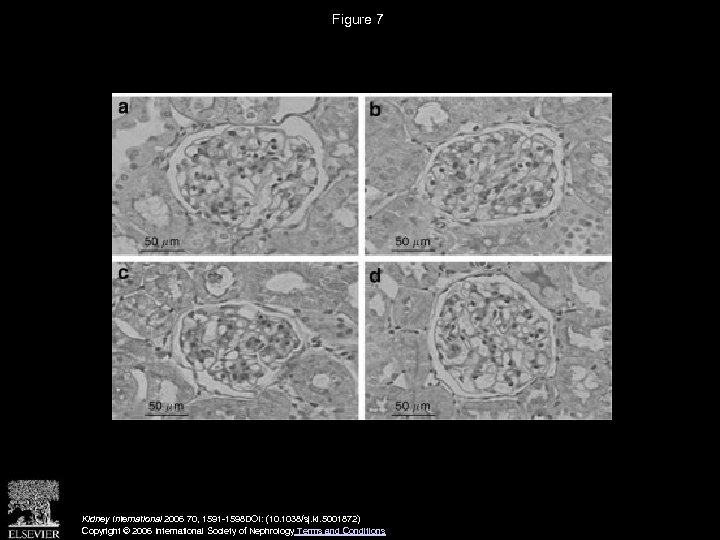

Figure 7 Kidney International 2006 70, 1591 -1598 DOI: (10. 1038/sj. ki. 5001872) Copyright © 2006 International Society of Nephrology Terms and Conditions